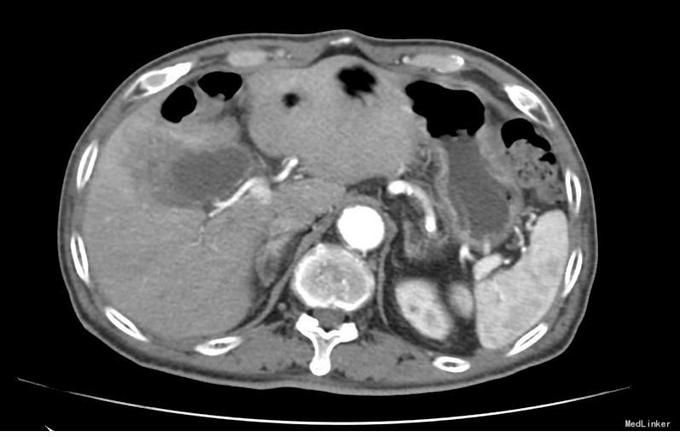

查体:右上腹轻压痛,无反跳痛、肌紧张。墨菲氏征弱阳性。 辅助检查:腹部CT:胆囊体积增大,壁增厚,以胆囊底部为著,增强扫描可见轻度强化,胆囊周围可见积液。MRI:胆囊增大,壁增厚,壁内可见多发结节状低信号灶。胆囊内可见泥沙样短T2信号影。